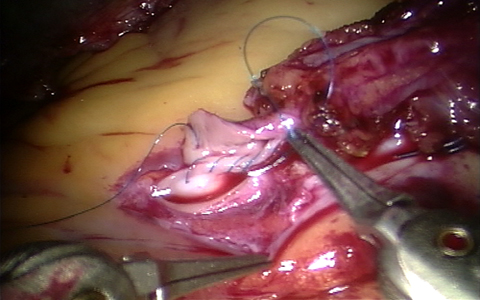

If the buildup of plaque has progressed, surgical procedure is often necessary. The most common procedure is coronary artery bypass surgery. Bypass surgery is the cutting of the blood vessels which is blocked by the fat. Then, the blood vessel is next join together again. The function of this surgery is to take away parts of the blood vessel that is blocked.